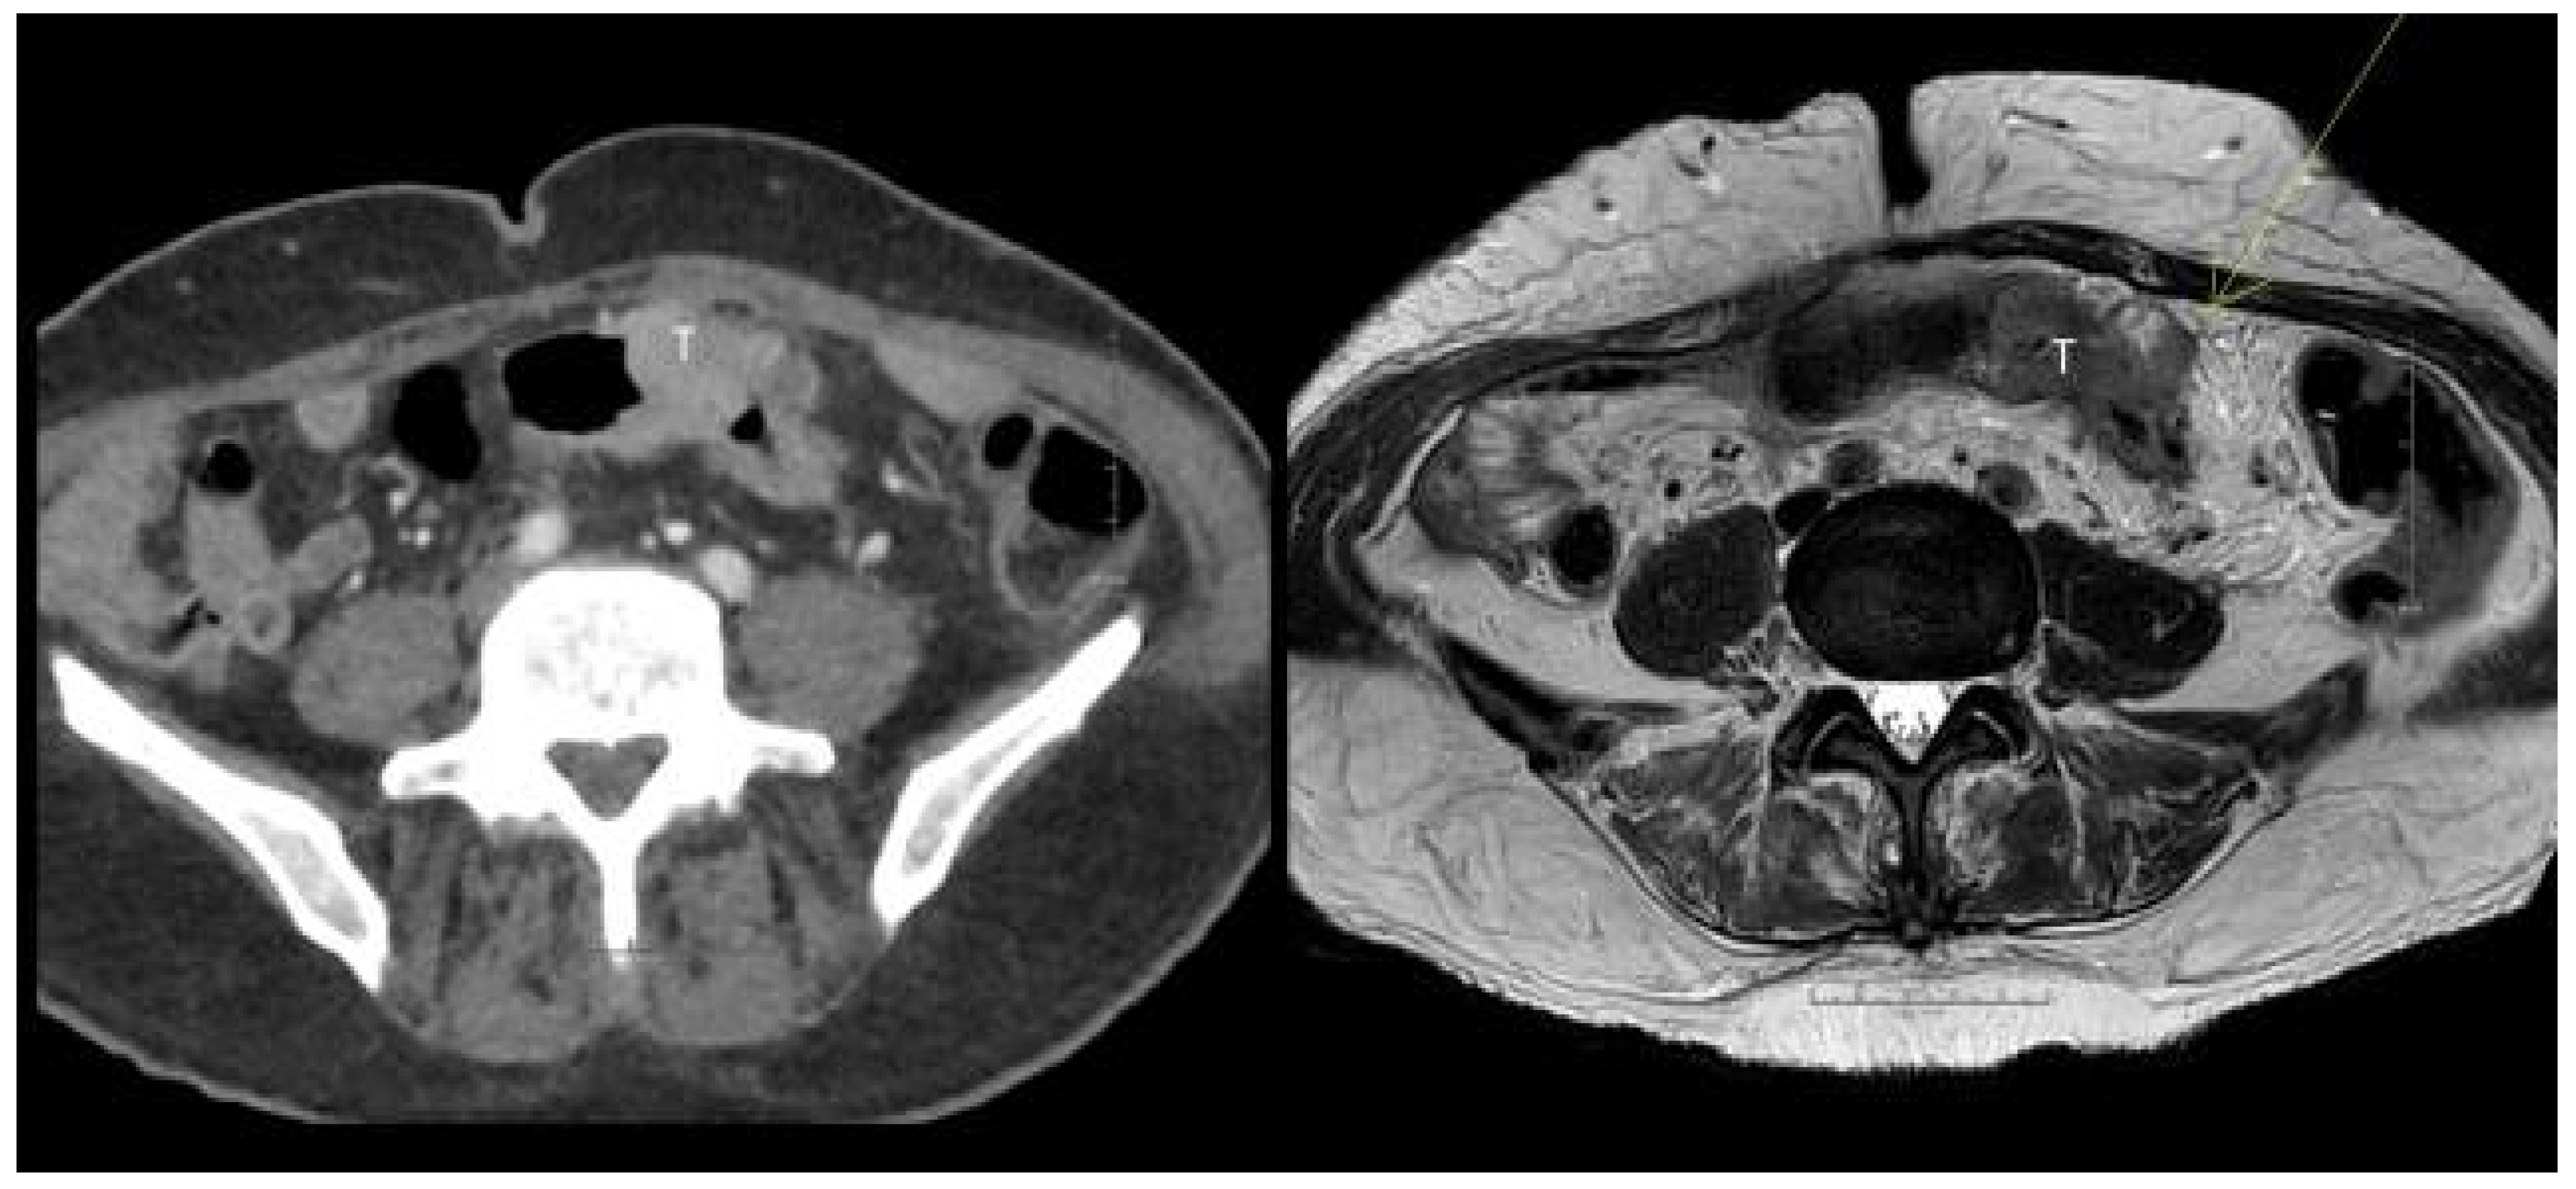

3. Results

3.2. Sensitivity and Specificity

| T1-3b vs. ≥T3c | 51.1 (36.0–66.1) | 80.8 (69.6–88.8) | 80.0 (65.0–89.9) | 91.8 (82.4–96.6) | p = 0.02 * |